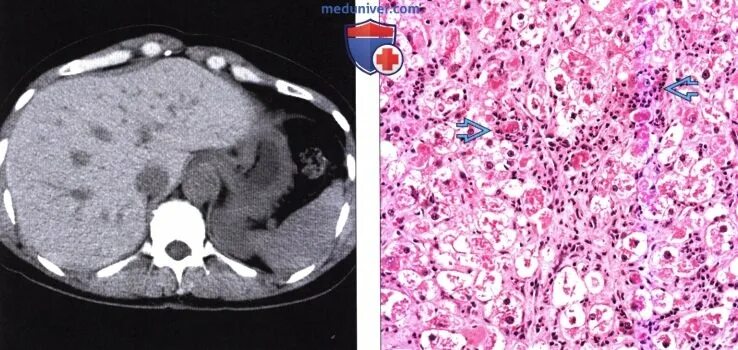

Цирроз на кт